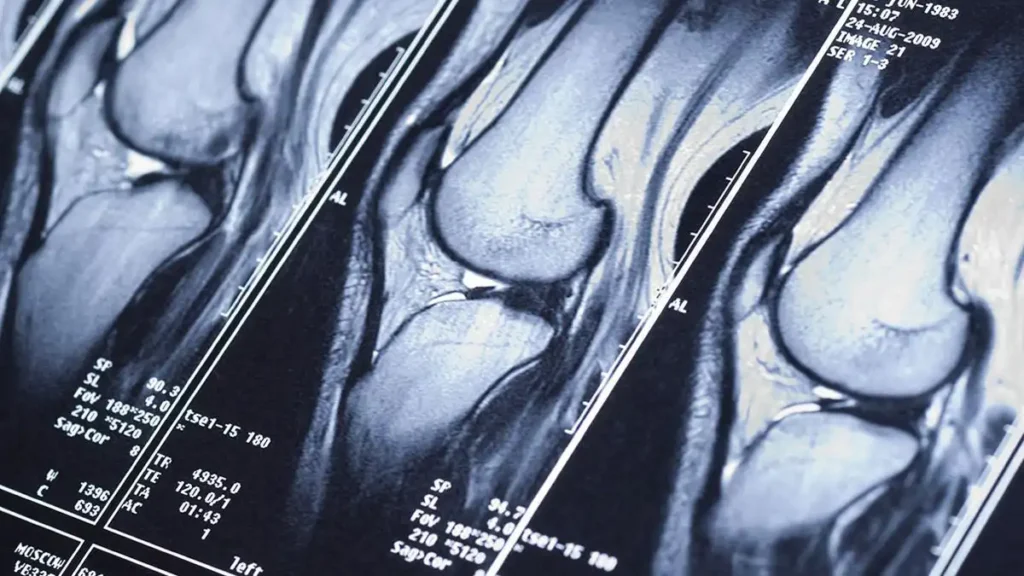

Pre-biopsy MRI may help avoid overtreating low-grade cancer.

The results could significantly improve the patient experience, expand access to MRIs, and potentially enable new use cases for MRI.

Imaging scientist Daniel Sodickson is collaborating with Facebook to make magnetic resonance imaging less burdensome for claustrophobic patients.

A new kind of MRI component in the shape of a glove delivers the first clear images of bones, tendons, and ligaments moving together, a new study finds.